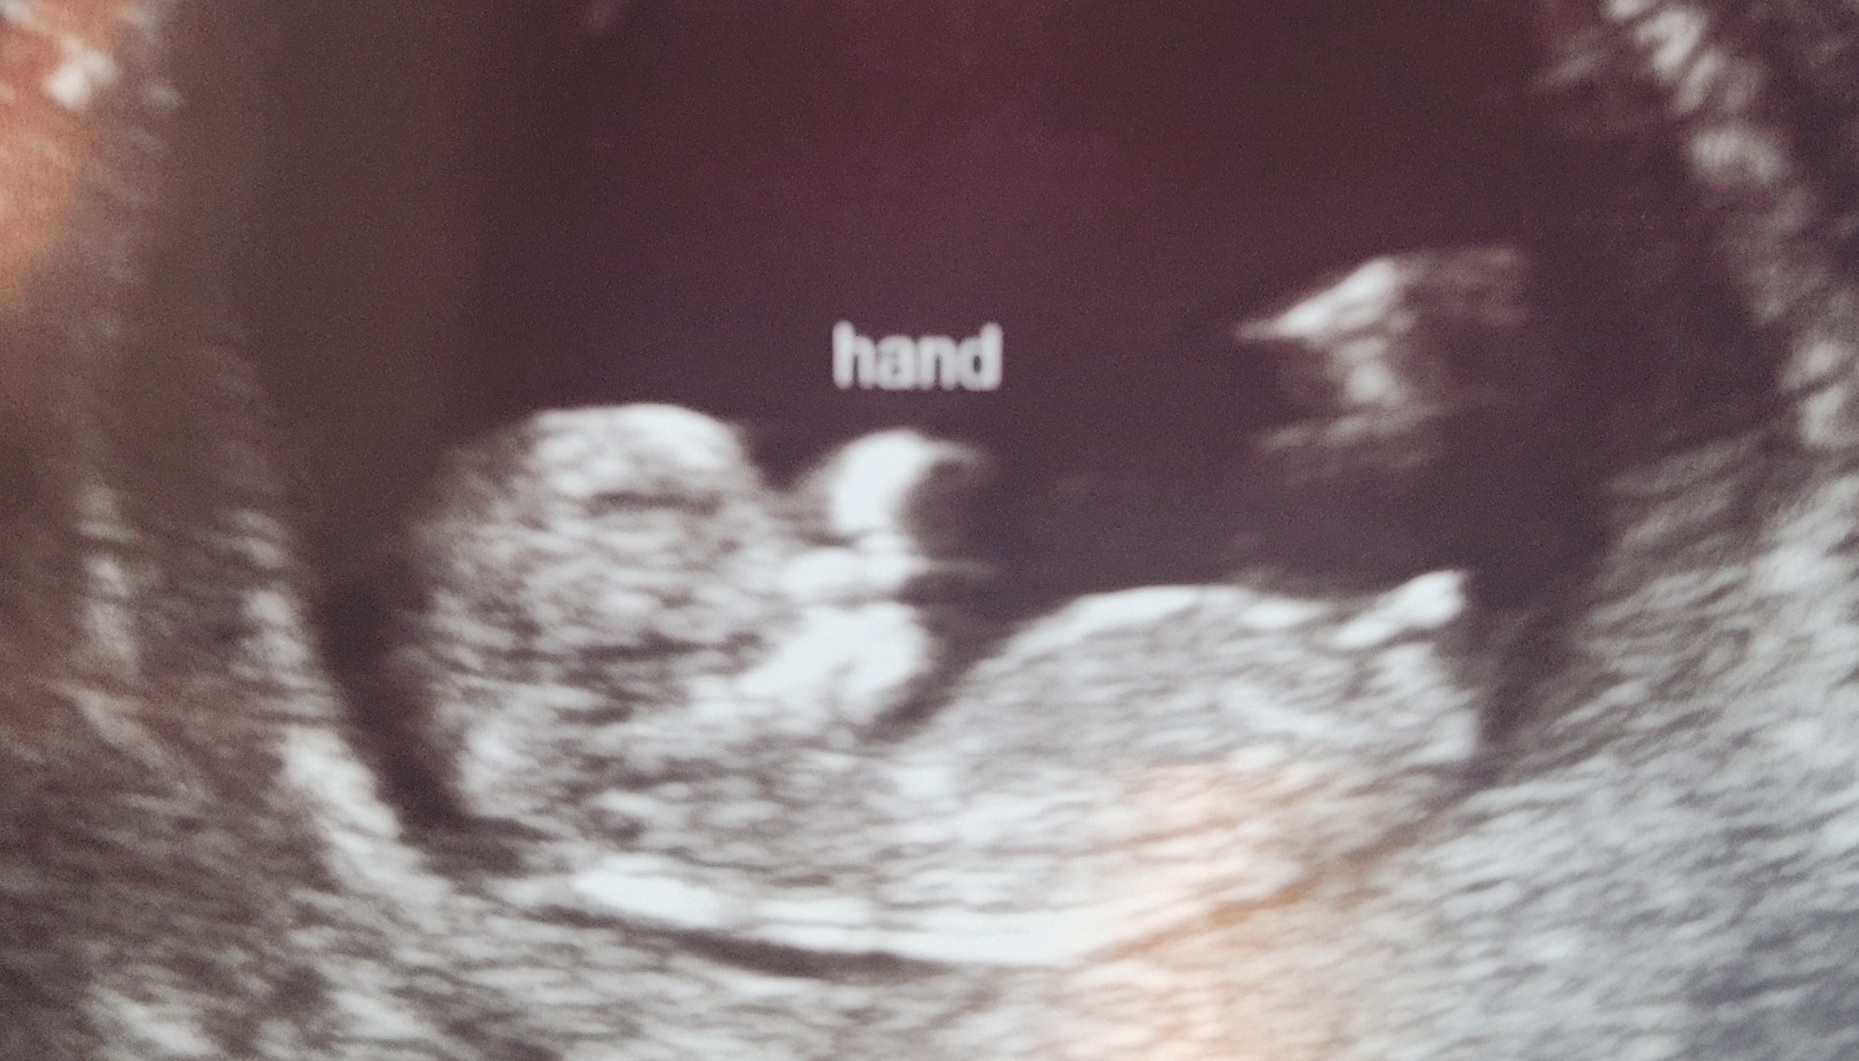

Attachment 42975

I’m getting boy vibes from the skull but like atomic said it’s too early so take my guess with a pinch of salt as skull theory isn’t reliable. The nub looks like it might rise but at the moment it’s flat due to the early gestation. I’d have a private scan in a couple of weeks if you can.